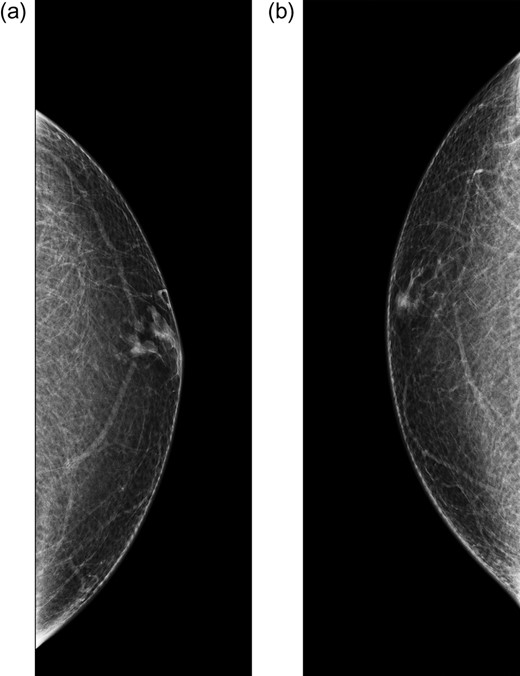

Bilateral mammogram demonstrated mild gynecomastia in both sides with no discrete mass or clusters of microcalcifications (Fig. 1). A follow-up ultrasound around the area of palpable concern did show a prominent duct with irregular contours at the 6:00 position in the left breast (Fig. 2). Excisional biopsy was recommended and a subareolar biopsy of the left breast was performed.

Diagnostic mammogram of the left (a) and right (b) breast demonstrates mild bilateral gynecomastia without discrete mass.